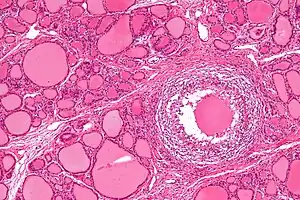

| Micrograph showing a granuloma in subacute granulomatous thyroiditis. H&E stain. | |

In subacute granulomatous thyroiditis, there is infiltration of neutrophils and other immune cells which cause damage to the thyroid follicular cells. The damage leads to formation of granulomas with multi-nucleated giant cells and associated fibrosis.[3][4][5][8] In contrast, subacute lymphocytic thyroiditis is characterized by an infiltration of lymphocytes causing damage to the thyroid gland, similar to Hashimoto's thyroiditis.[8]